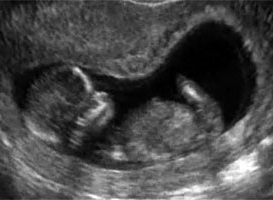

Нам все замерили: все у Кнопика в порядке! Все параметры соответствуют сроку, ВПР не обнаружено! Дали фотографию: наш Кнопик уже так подрос! Ручки, ножки, носик...Все на месте!

Вот наше сокровище:

Срок по УЗИ поставили, как и на первых УЗИ, на неделю больше: 12,3 недель. ПДР не сдвинули. Вес Кнопика 28 г, а рост 10,2 см.